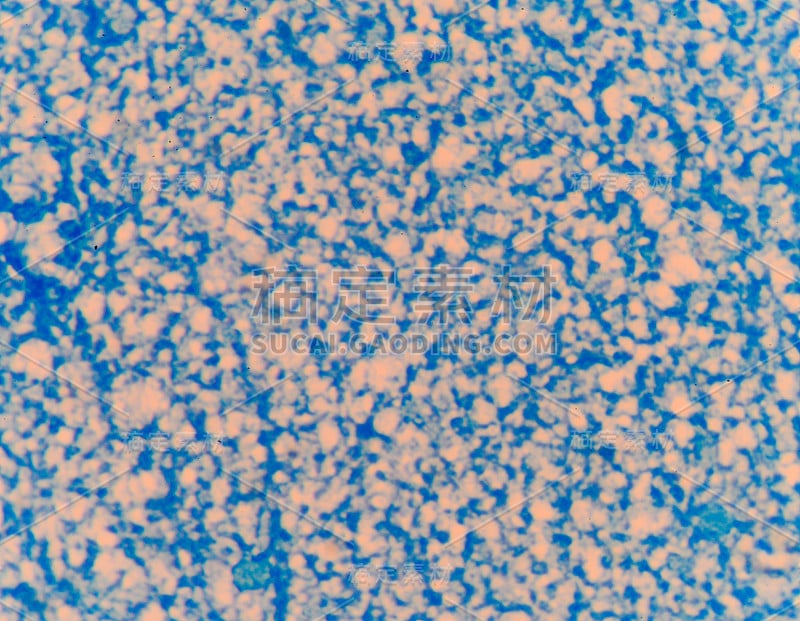

革兰氏染色剂详情

JPG